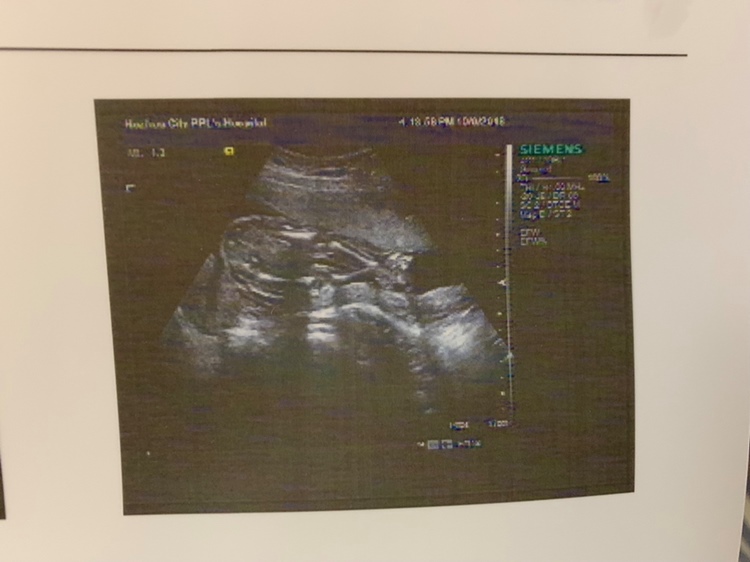

孕16周+1天